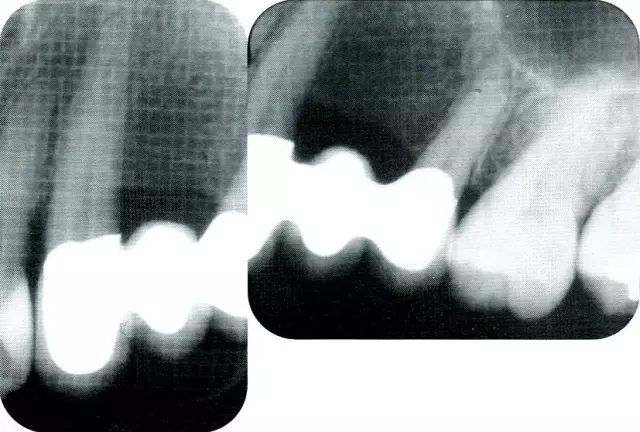

640.webp (6).jpg

▲圖7-7  術(shù)前,術(shù)后的x片。確認(rèn)出現(xiàn)骨再生,牙槽嵴硬線。